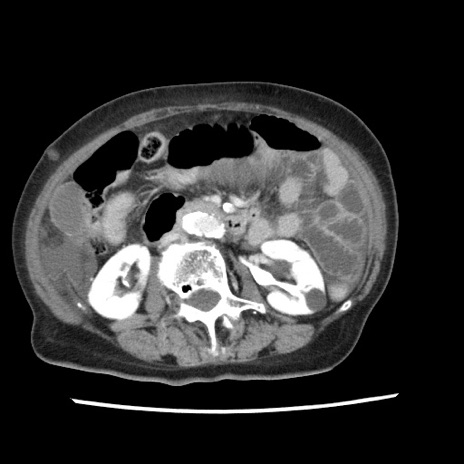

【症例】80歳代女性

【主訴】腹痛

【現病歴】8時間前から腹痛あり来院。

【既往歴】糖尿病、脂質異常症、子宮体癌にて子宮全摘術

【身体所見】意識清明・会話良好だが腹痛で苦悶様、全腹部にわたって反跳痛と圧痛あり

【データ】WBC 13600、CRP 0.14、LDH 224、CK 90